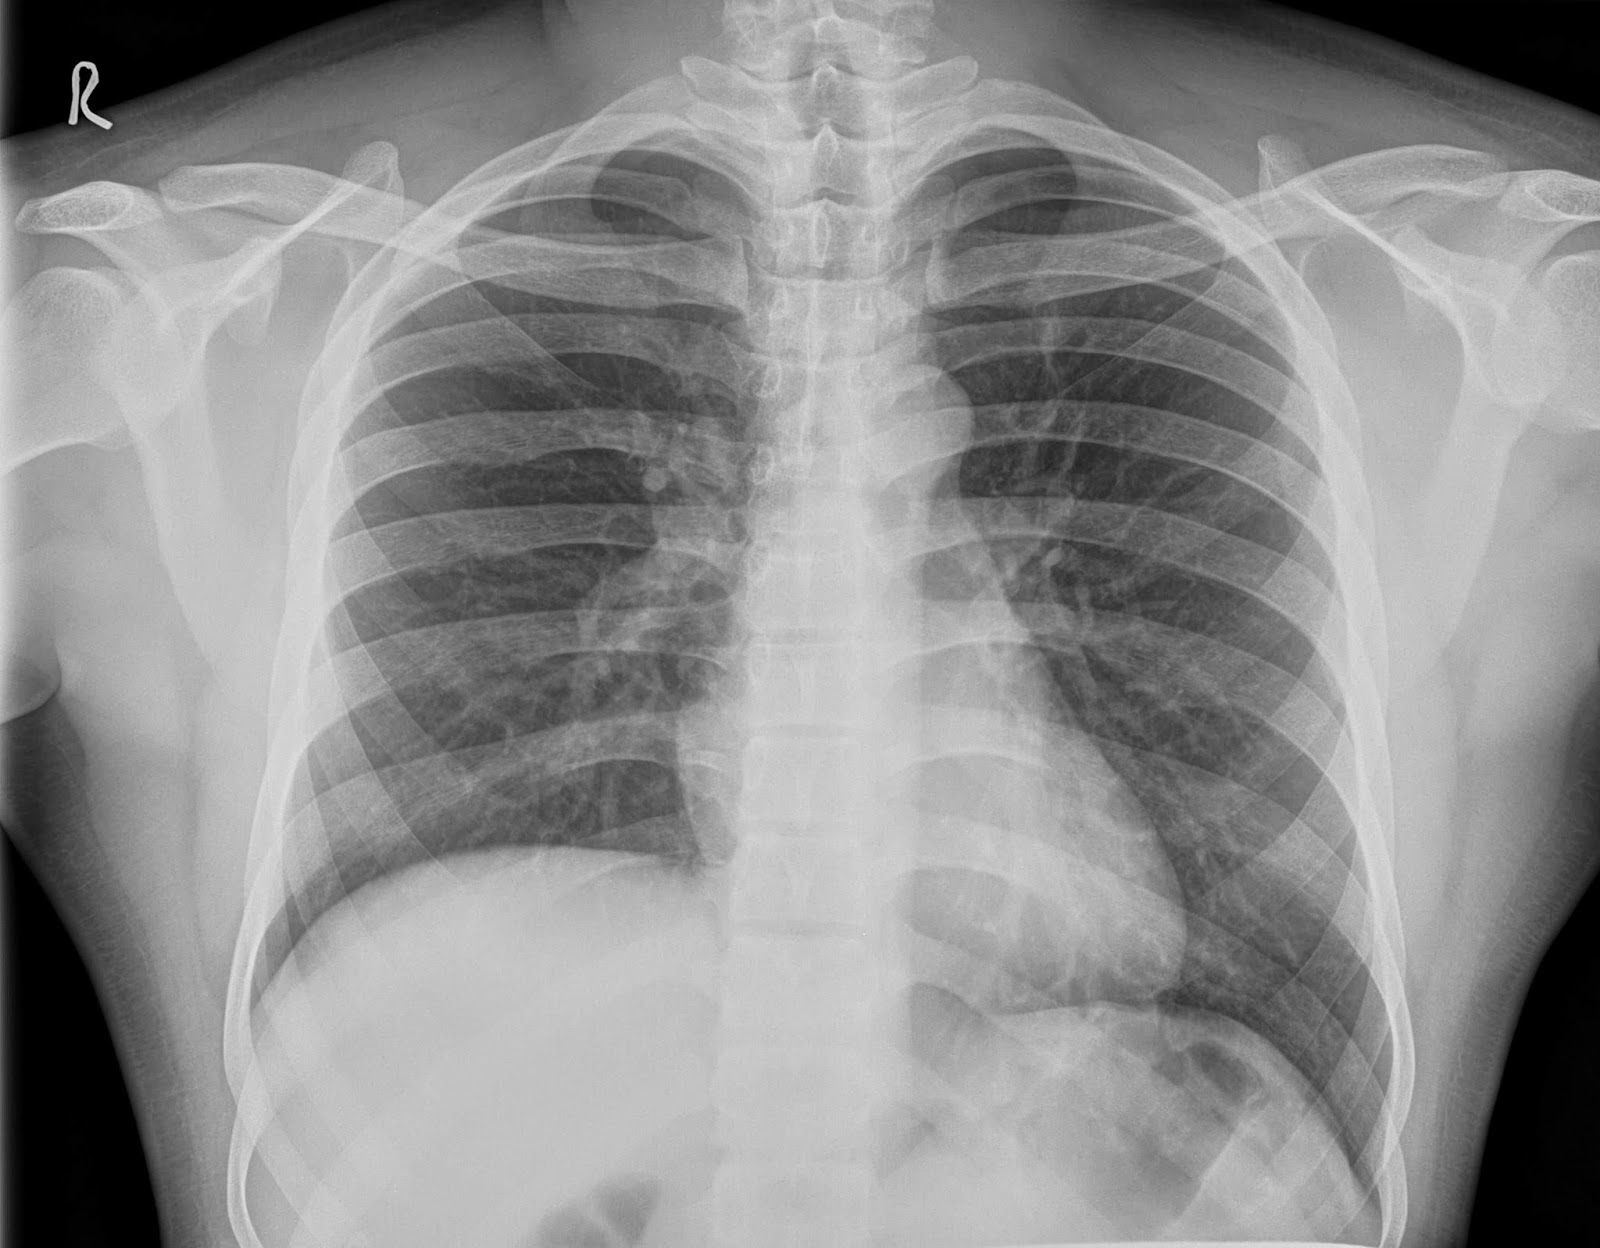

From ddxof.com

Differential Diagnosis of Elevated Hemidiaphragm Diaphragm Elevated On Left Side elevated hemidiaphragm is a condition where one portion of the diaphragm is higher than the other. elevated hemidiaphragm is a condition where one portion of the diaphragm is higher than the other. elevated hemidiaphragm is a condition where one portion of the diaphragm is higher than the other. if the left side is paralyzed, both hemidiaphragms. Diaphragm Elevated On Left Side.

From radiologycases.my

Elevated hemidiaphragm Radiology Cases Diaphragm Elevated On Left Side elevated hemidiaphragm is a condition where one portion of the diaphragm is higher than the other. unilateral diaphragm paralysis is often first suspected after the finding of an abnormally elevated hemidiaphragm on a. elevated hemidiaphragm is a condition where one portion of the diaphragm is higher than the other. an elevated hemidiaphragm may result from direct. Diaphragm Elevated On Left Side.